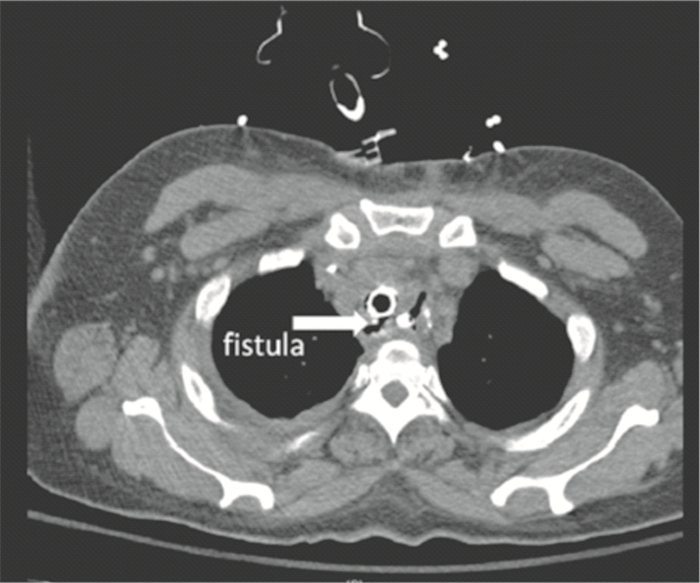

臨床表現因嚴重程度各異,從輕度至危及生命的膿毒癥而不同。瘺最常見的早起癥狀是咳出進食物以及誤吸胃內容物引起的呼吸困難。這些可進展為反復吸入性肺炎及膿毒血癥。有些患者在早期可有少許表現,其他患者則表現為失代償期的化學性伴/不伴細菌性肺炎。食管造影可表現為口服的造影劑進入氣道,但在瘺較小時可能沒有診斷價值。如果臨床高度懷疑或食管造影顯示有瘺,則需進一步內鏡確診。內鏡需觀察上段食管,吻合口,腔道及氣道。吻合口和胃吻合線是瘺的常見部位,需仔細觀察,但有時食管側小的瘺口難以明確。腔道內重疊的黏膜可以遮蔽小的開口。在氣道側可以更好地確診瘺以及瘺的大小和部位。除非患者處于術后的早期階段,否則很重要的一點是,均需瘺活檢以明確是腫瘤復發還是良性病變。如果仍處于術后早期階段,需行CT檢查來明確周圍有沒有液體積聚,如果有,則需要引流。瘺本身偶爾可經CT確診(圖 1),但因敏感性和特異性均不高,故診斷不能依賴CT。